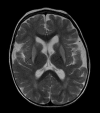

Difficult management of glucose homeostasis in a 21-month-old child with type 1 diabetes and unknown glutaric aciduria type I: a case report